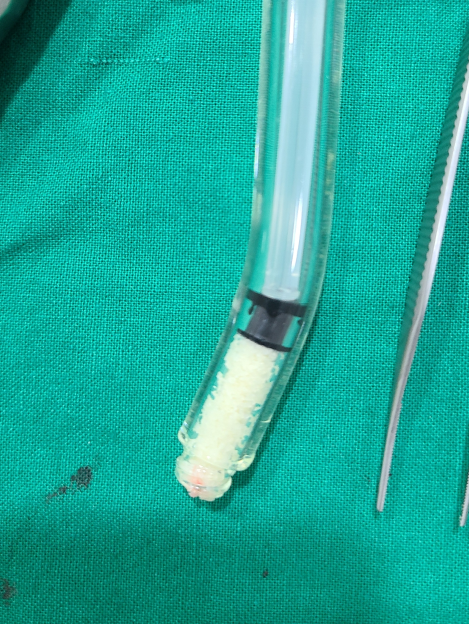

저희는 수술 과정도 자세하게 사진으로

기록하는 병원입니다.

사기치지 않습니다.

이 뽑은 사진

염증 제거한 사진

사용한 뼈

모두 찍어 보여드립니다.